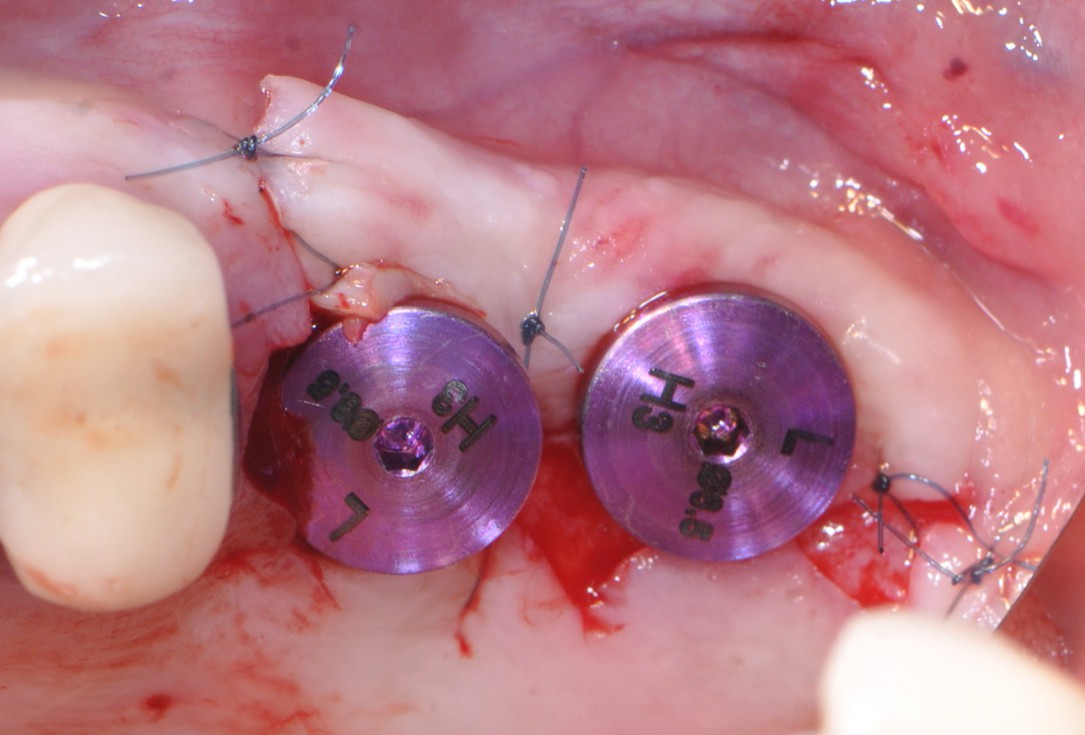

14/16 - Healing screws placement

One-stage sinus lift - Dr. V. Kalenchuk